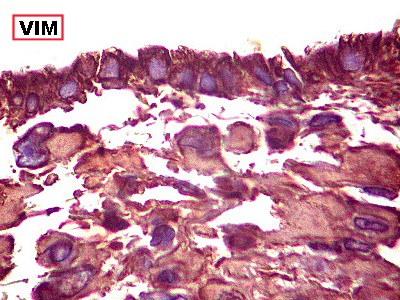

| VIM.

Positiva no citoplasma das células neoplásicas. Filamento

intermediário do citoplasma de expressão ubiquitária. |

Destaca

núcleo excêntrico, deslocado pelo corpúsculo rabdóide. |

VIM.

Positivo no epêndima do III ventrículo. Células neoplásicas

subjacentes. |